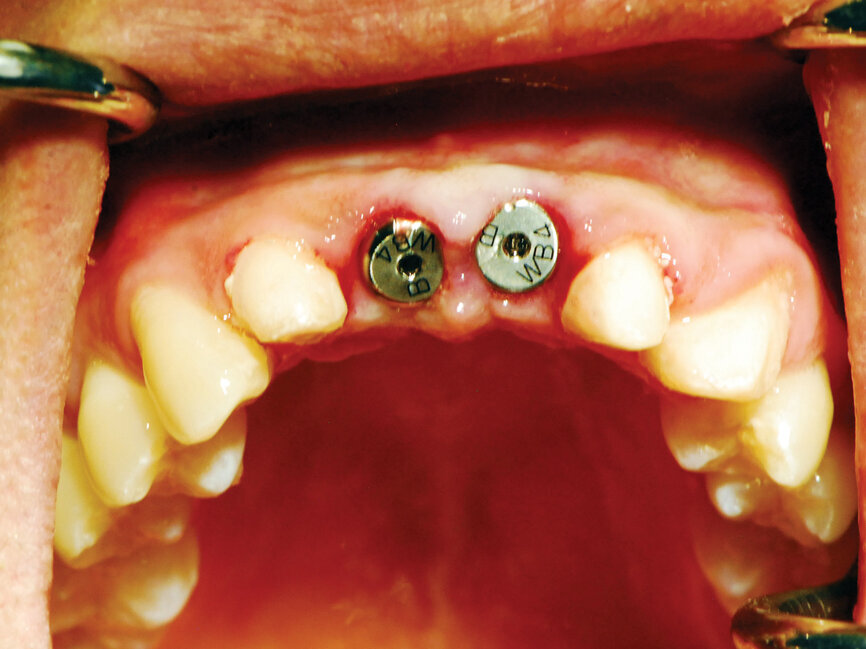

Fig. 9: Uncovery of the implants and healing screws exposed. (Photo provided by Dr. Gregori M. Kurtzman)

Fig. 10: Healing abutments placed into the implants. (Photo provided by Dr. Gregori M. Kurtzman)

The process cuts the desired soft tissue and coagulates any bleeding from the cut edges. This was then repeated on the second implant (Fig. 9). Open tray implant impression abutments were placed into the implants and seating verified radiographically. An impression of the maxillary arch was taken utilizing Aquasil heavy body VPS (Dentsply Sirona, Milford, Del.) in a Mira Advanced Implant tray (Hager Worldwide, Hickory, N.C.) and Aquasil Ultra syringed around the preparations and implant abutment heads.

Healing abutments were placed into the implants (Fig. 10). The previously placed provisional bridge was tried in and modified at the pontics to allow the bridge to fully seat over the healing abutments and luted with a provisional cement (Fuji Temp LT, GC America, Alsip, Ill.).